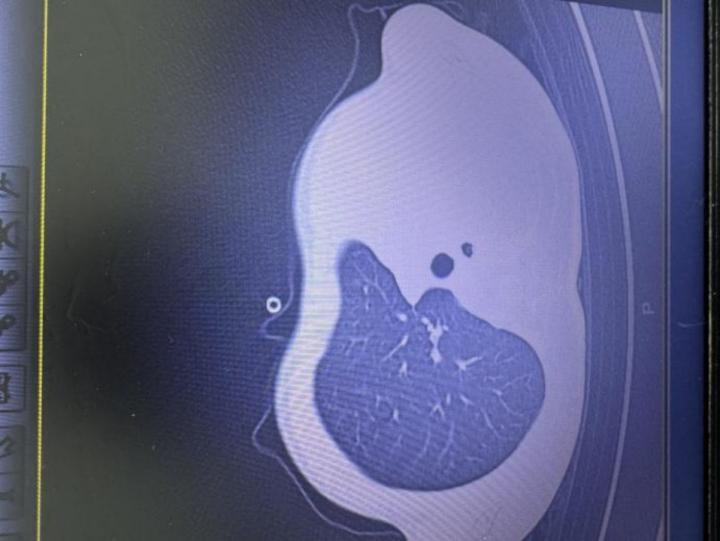

急診檢查結(jié)果讓醫(yī)護(hù)人員瞬間緊張:驗(yàn)血顯示炎癥指標(biāo)大幅上升,胸片更發(fā)現(xiàn)左側(cè)肺葉幾乎“不工作了,影像學(xué)中變成大片白色,即通常所說的“白肺”,意味著肺功能嚴(yán)重受損,孩子已經(jīng)缺氧,隨時(shí)有窒息危險(xiǎn)。

影像顯示肺白了一半